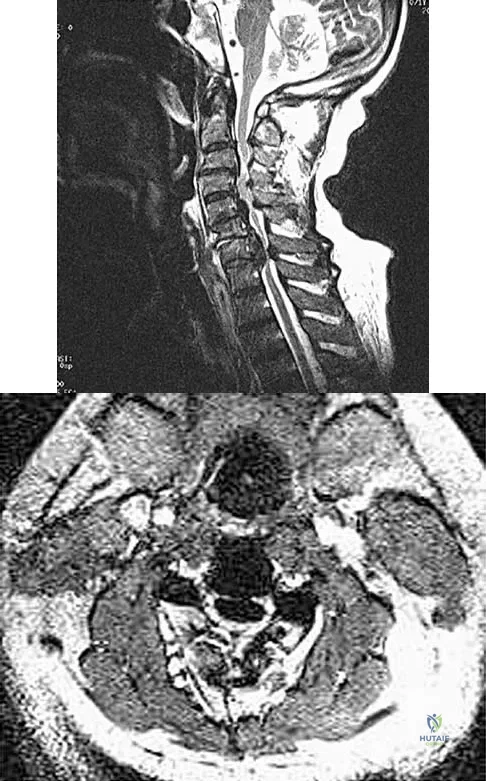

Question 62

An Asian 45-year-old man has bilateral upper extremity dysfunction. Figure 35a shows a T2-weighted sagittal MRI scan of the cervical spine, and Figure 35b shows a T2-weighted axial MRI scan at the level of the C3 vertebral body. What is the most likely pathologic process?

Explanation